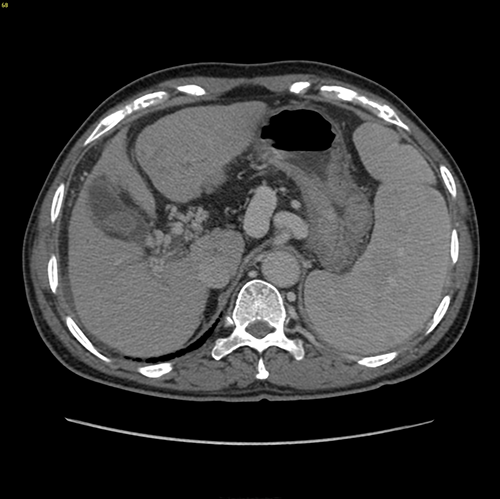

门脉高压、门静脉海绵状变、S3肝癌------S3切除、脾切除